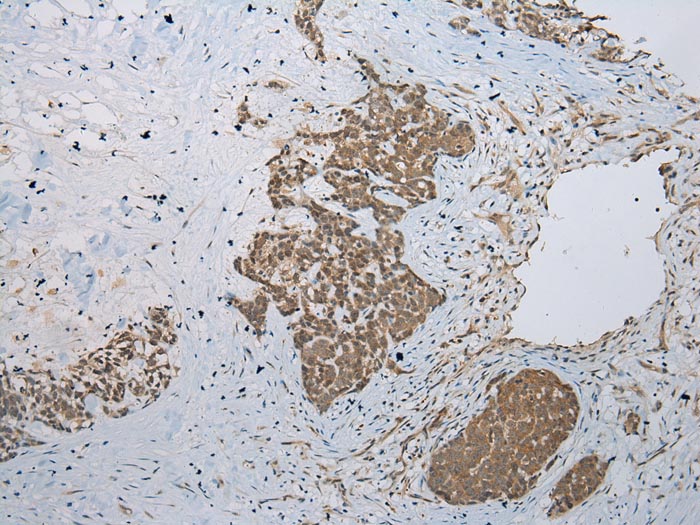

Immunohistochemical analysis of paraffin-embedded Human Esophagus cancer tissue using #43461 at dilution 1/200.